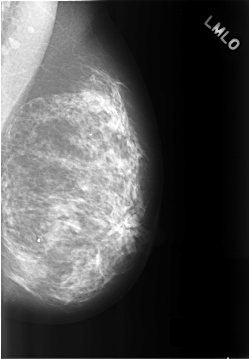

C_0307_1.LEFT_MLO

C_0307_1.LEFT_CC